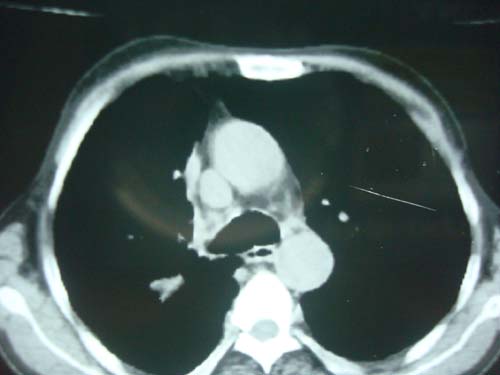

男性,45岁,胸疼,低热,抗炎治疗后症状缓解拍片检查发现左上肺有高密度灶,考虑结核,做ct示条件有限采集了部分图像,图像质量差请谅解

病灶有分叶,毛刺,考虑肺癌可能性大,建议穿刺。

病灶有分叶 毛刺 左侧叶裂上移 考虑肺癌可能性大 建议穿刺

右上肺结核,左上肺周围型肺癌可能性大

考虑两肺上叶继发性肺结核;肺气肿(多发肺大泡)。

建议:追踪复查。

问下职业史,矽肺结节也说不定。

团块状病灶,病灶周围长毛刺及灶周肺气肿。